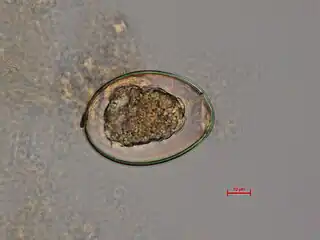

a-c)Diphyllobothrium sp. eggs

Diphyllobothrium latum - fertilized egg